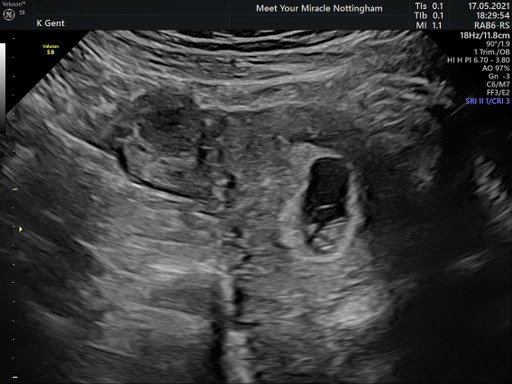

Guineapiggiesmalls · 17/05/2021 19:31

@dano99 Try not to worry too much. Early scans are notoriously difficult to date. The same thing happened to me with my first baby, I excitedly booked an early scan for 7 weeks only to be told that either I'd got my dates wrong or the baby had stopped developing. I had a further scan 10 days later to show everything was fine, and saw a little heartbeat.

Early scan yesterday she thinks 7 weeks and a bit ish gave me a due date around January 2nd 2022. Although I put this in online calculator and it gives me a DD of dec 26th 2021 Confused

Glad the scan went well @MrsGxx .. 7wks was in line with what you are thinking?

I suppose the due date really depends on if it is 6.5wks or 7.5wks 7ish could mean anything in between & at this stage it's very early to confirm dates accurately.

Prob best getting the later date in your head.. easier if it's brought forward at the 12wk scan then pushed put an extra week lol

@LilmissCa I was expecting to be 7-8 weeks I wasn’t 100% sure as I had been on the pill and came off in February with no period so really wasn’t sure. I guess wanting to be further along is quicker to 12 weeks and more out of the woods as you would say.